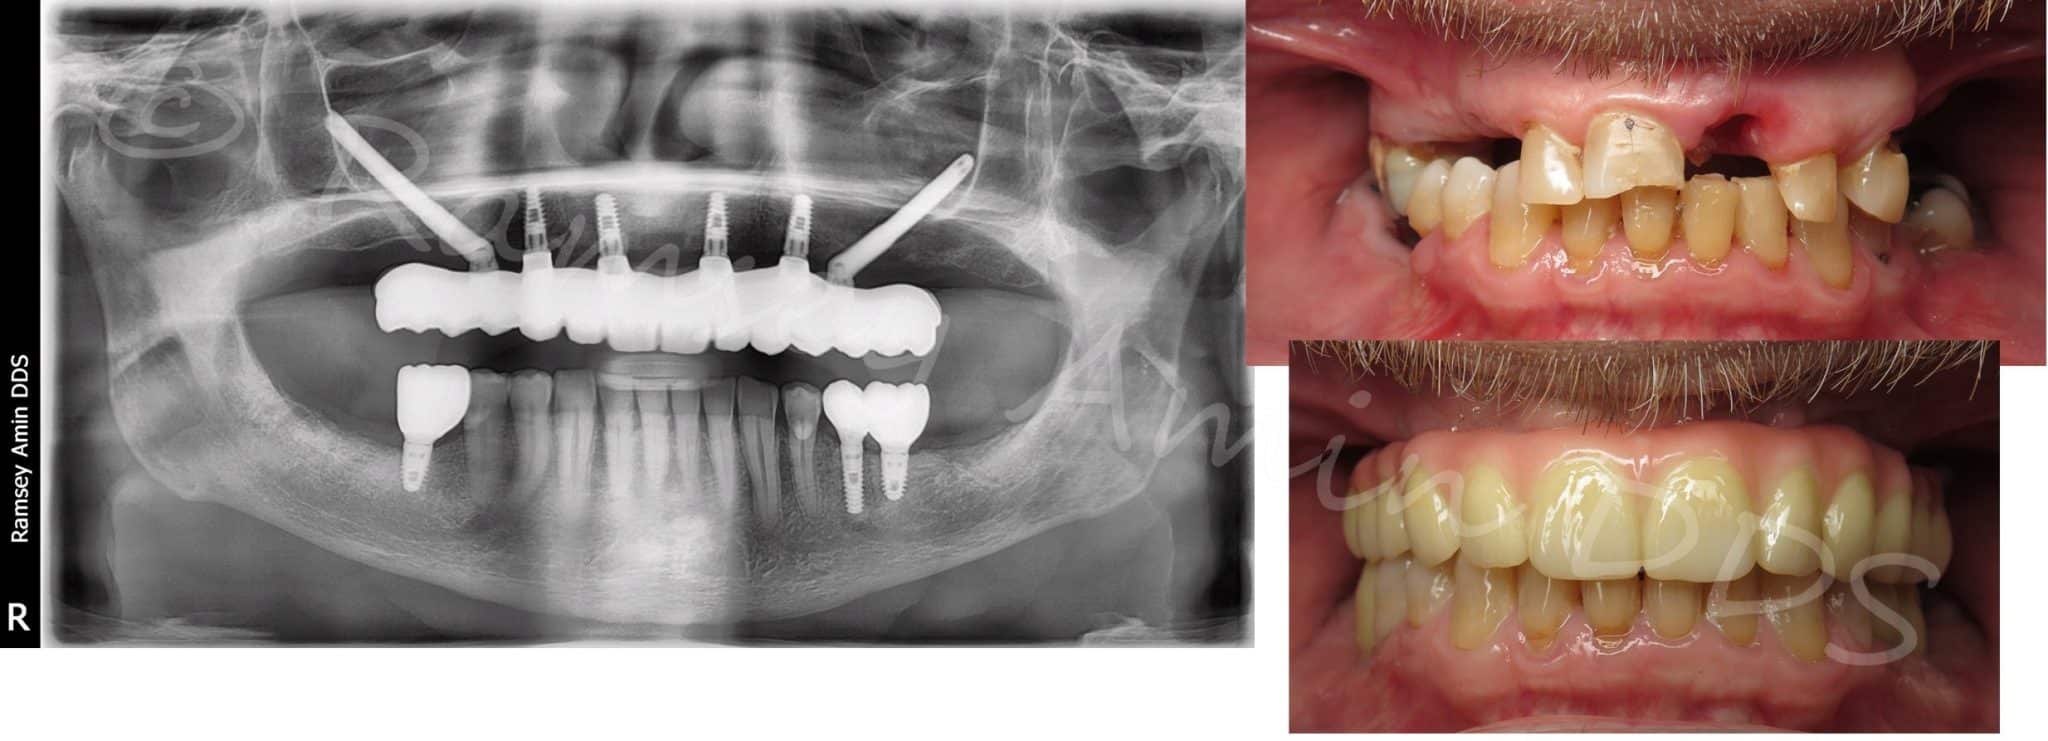

Zygomatic Implants Ramsey A. Amin, DDS What Is Zygomatic Dental Implants this article provides consensus statements and clinical recommendations for the use of. zygomatic implants are a dental implant treatment option offering hope to individuals who once faced limited options due to severe. They are longer than traditional. zygomatic dental implants are a specialized dental solution for people with severe bone loss or resorption in the upper jaw.. What Is Zygomatic Dental Implants.

Quad Zygomatic Dental Implants To Replace Dentures Without Bone